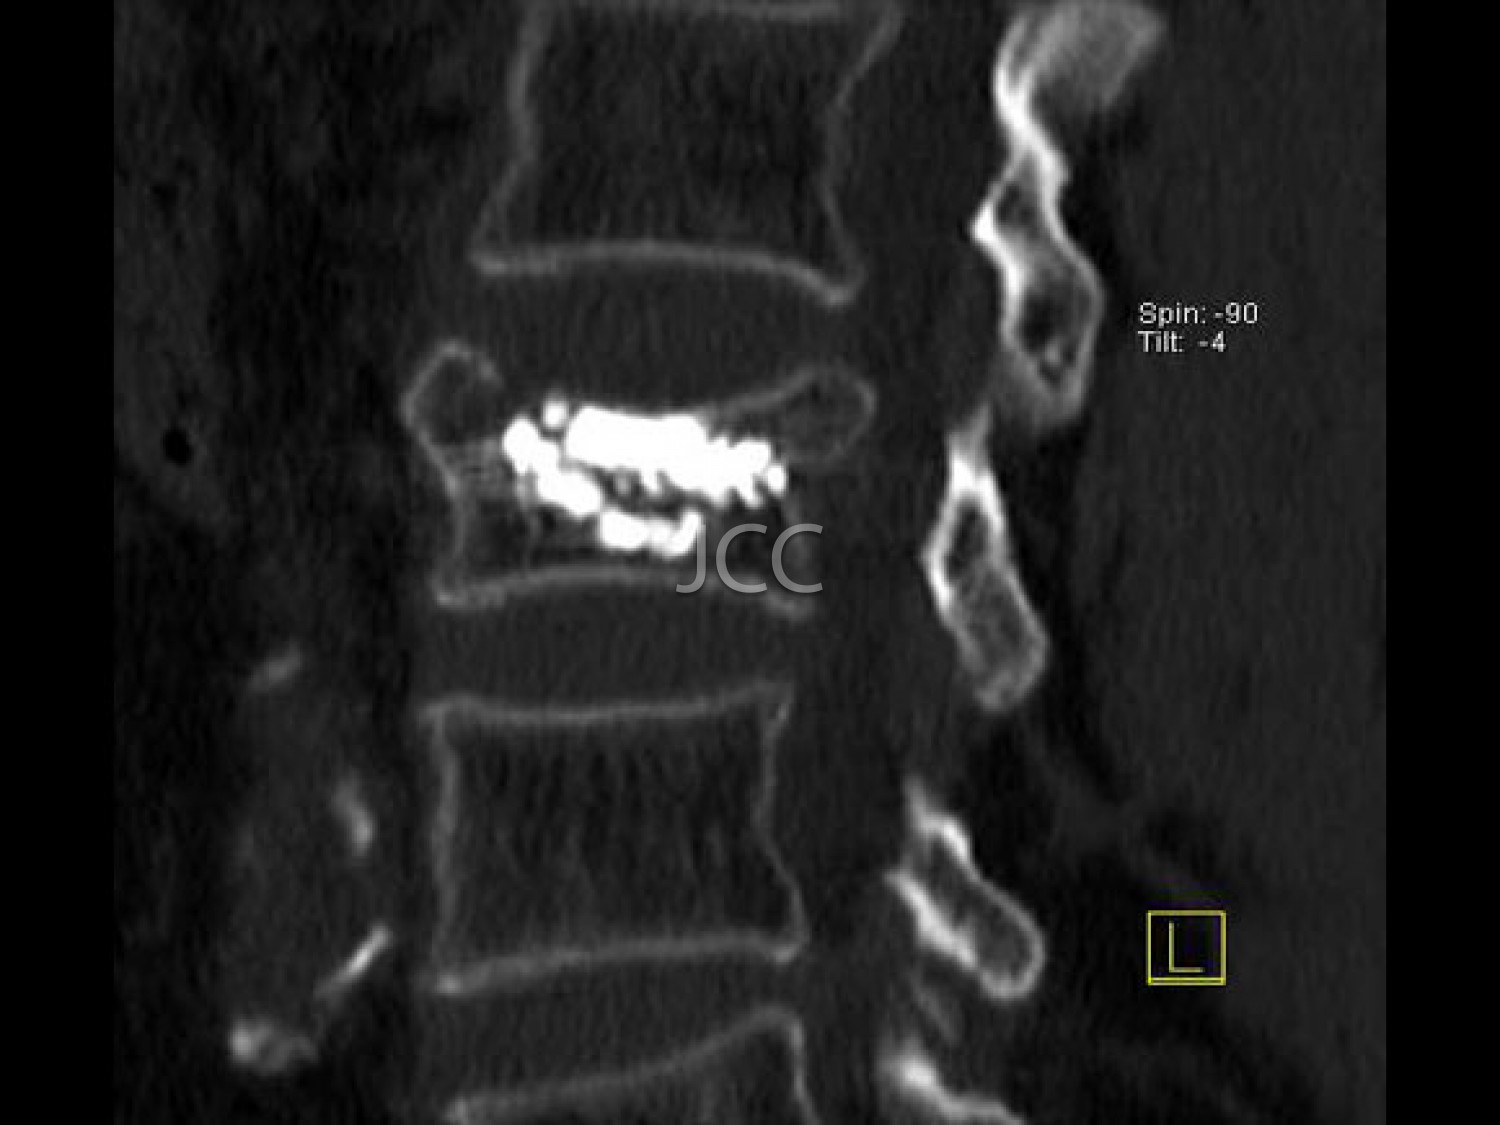

Vertebroplastia